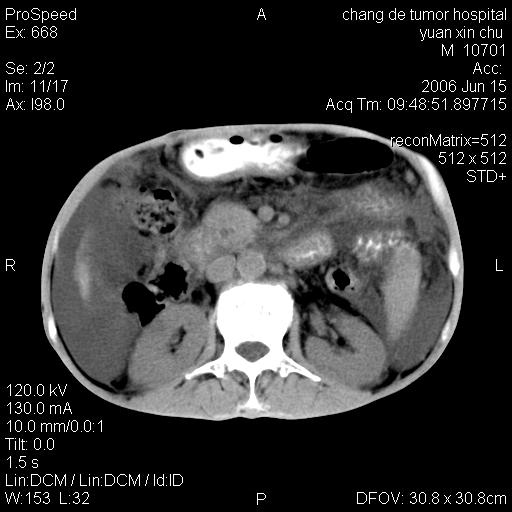

以下是引用qian在2007-4-23 19:06:00的发言:[br]胰腺体积增大,轮廓欠规则,肝轮廓波浪状改变,肝裂增宽,肝周、脾周有液性密度,腹膜后肿大淋巴结,考虑1、胰腺癌伴腹膜后淋巴结转移;2、肝硬化伴腹水。

以下是引用卜一在2007-4-23 20:12:00的发言:[br]胰腺体积增大,轮廓欠规则,肝轮廓波浪状改变,肝裂增宽,肝周、脾周有液性密度,腹膜后肿大淋巴结,考虑1、胰腺癌伴腹膜后淋巴结转移;2、肝硬化伴腹水。支持!